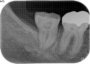

1)レントゲン撮影

2)CT撮影